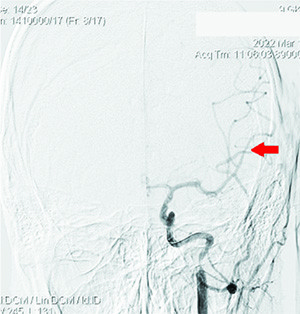

Проведена диагностика: определялась окклюзия несколько дистальнее устья ВСА слева, коллатеральное заполнение сосудов левой гемисферы из правой ВСА и позвоночных артерий, локальная окклюзия ветвей первого порядка левой СМА после бифуркации (см. рис. 2 и 3).

Принято решение о реканализации ВСА, механической тромбэкстракции из СМА слева. По проводнику селективно в ВСА установлен интродьюсер направляющий катетер Destination F7 (см. рис. 4 и 5).

При контрольной ангиографии визуализировалось восстановление кровотока по СМА слева (см. рис. 6) (время реперфузии 13:33), mTICI 3. Катетеры извлечены, интродьюсер промыт, удален. Пункционное отверстие ушито системой ProGlide.